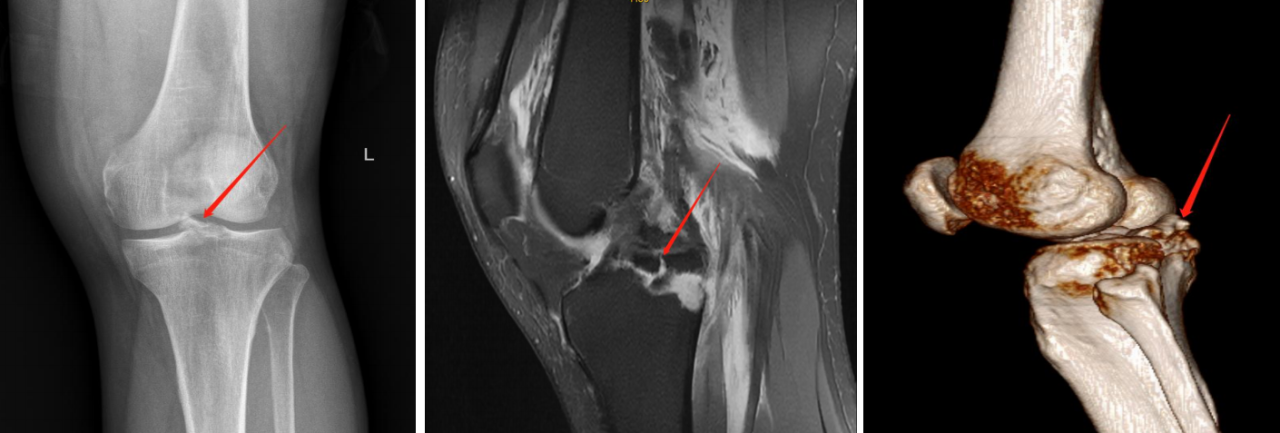

后交叉韧带止点撕脱骨块

3.分型及术式

我们的分型

总结我科临床资料,提出后交叉韧带止点撕脱骨折分型,并据分型设计

相应术式选择!依据:

1.CT与MRI矢状位骨折块长度(BC);

2.矢状位撕脱骨折前后距与胫骨平台前后距比例(AE/AD);

Ⅰ型:撕脱骨折块BC小于15mm,AE/AD小于1/2;

Ⅱ型:撕脱骨折块BC大于/等于15mm,AE/AD小于1/2,常见;

Ⅲ型:撕脱骨折块BC大于15mm,AE/AD大于或等于1/2;

ⅢA型:多块撕脱骨折块,BC大于15mm,AE/AD大于1/2;

ⅢB型:骨折块合并半月板撕裂,BC大于15mm,AE/AD大于或等于

1/2。

ⅢC型:髁间棘陈旧性撕脱骨折, BC大于15mm,AE/AD大于或等于

Ⅲ型:撕脱骨折块;BC>15mm;AE/AD≥1/2。

术式:双袢+后叉前建立骨道

步骤: 明确骨折、建立骨道、置袢复位骨折

ⅢA型:多块撕脱骨折块,BC>15mm,AE/AD>1/2;

术式:双袢(后叉前建立骨道)+高强线

步骤: 明确骨折、建立骨道、引入袢+预置高强线

步骤: 建立平台骨道、复位收袢

分型及术式

ⅢB型:多块撕脱骨折;合并半月板撕裂;BC>15mm;AE/AD≥1/2。

术式: 双袢(后叉前建立骨道)+骨道固定

合并内侧半月板放射裂

撕脱骨折、内侧半月板放射裂

半月板骨道固定、双袢固定撕脱骨折